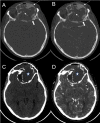

Juvenile psammomatoid ossifying fibroma (JPOF) is a rare, benign type of ossifying fibroma. JPOFs predominantly present as rapidly growing masses with a high recurrence rate. We report a 40-year-old male patient who suffered from a large tumor with multiple invasions into the paranasal sinuses. Total excision was performed, and significant relief of clinical symptoms was recorded after 4 months of follow-up. Multi-departmental management involving radiologists, neurology surgeons, craniofacial surgeons, pathologists, and otolaryngologists is vital for JPOF treatment. First-line treatment options include total or partial resection, depending on the patient's condition.